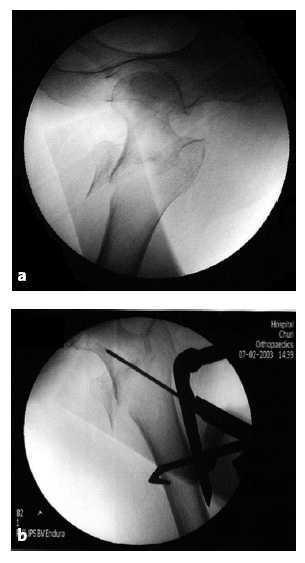

Figuras 4a y b

Imagen de intensificador de imágenes que muestra la fractura reducida en ambos planos, AP (a) y lateral (b). El rectángulo más oscuro representa el dispositivo de reducción (flecha).

Sobre la imagen del fémur proximal en el televisor colocamos plantillas de plástico para comprobar que el ángulo cérvico-diafisario es de 135º y comprobaremos que el tornillo cefálico distal se encuentra a 2-3 mm proximal al calcar femoral. Si el ángulo es inferior a 135º realizaremos más tracción.

La flecha en la imagen fluoroscópica indica el punto donde debe introducirse la aguja espinal para marcar la primera incisión.